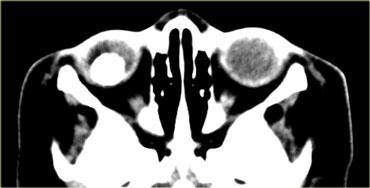

Bệnh mắt tuyến giáp

Hãy quan sát các hình ảnh bên trái, mô tả chúng và đưa ra chẩn đoán phân biệt, đồng thời tạm thời bỏ qua tiêu đề của đoạn này.

Chẩn đoán là bệnh mắt tuyến giáp và chẩn đoán phân biệt là giả u hốc mắt.

Chúng ta sẽ thảo luận ngay sau đây về cách phân biệt hai bệnh lý này.

Nguy cơ lớn nhất của bệnh mắt tuyến giáp là bệnh lý thần kinh thị giác do chèn ép, có thể do chèn ép trực tiếp bởi các cơ hoặc do thiếu máu cục bộ gây ra bởi sự chèn ép các mạch máu.

Đặc điểm then chốt cần tìm kiếm là đỉnh hốc mắt.

Nếu không thấy mô mỡ xung quanh đỉnh hốc mắt, khả năng cao có tình trạng chèn ép.

Những bệnh nhân này được điều trị bằng phẫu thuật giải áp qua nội soi, trong đó thành trong của hốc mắt (tức là lá giấy – lamina papyracea) được phá vỡ.Giả u

Bệnh có thể ảnh hưởng đến mọi thành phần của hốc mắt: cơ, gân, mô mỡ, thần kinh thị giác, bao thần kinh, tuyến lệ, v.v.Điểm phân biệt then chốt giữa giả u và bệnh mắt tuyến giáp là trong giả u, không chỉ các cơ mà cả các gân cũng bị tổn thương.

Những bệnh nhân này cảm thấy đau khi cử động mắt do các gân bị kích thích.

Trên hình ảnh bên trái ngoài cùng, hãy chú ý sự thon nhỏ dần của cơ bị phù nề tại điểm bám gân ở bệnh nhân mắc bệnh mắt tuyến giáp.

Bên cạnh đó là hình ảnh của bệnh nhân mắc giả u.

Hãy chú ý rằng tình trạng phù nề lan rộng đến tận điểm bám gân.Bệnh lý ngoài nón cơ